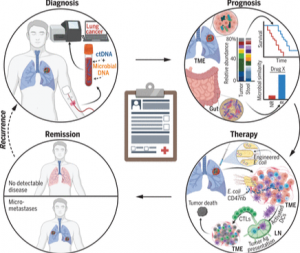

ToggleDe la cancérogenèse à la thérapie anticancéreuse

Plus récemment, des bactéries ont été mises en évidence au sein des tumeurs elles-mêmes : comprendre leur nature, l’origine de leur présence et leur influence sur le tissu cancéreux pourrait apporter de nouvelles pistes thérapeutiques.

Une action sur l’efficacité des traitements

L’immunothérapie anticancéreuse bénéficierait aussi d’un coup de pouce de la part du microbiote : cette approche thérapeutique vise à déverrouiller certains points de contrôle immunitaires qui freinent les défenses de l’organisme face aux cellules tumorales. Si elle peut être très efficaces, beaucoup de patients n’y sont pas répondeurs. L’une des causes résiderait dans la composition de leur microbiote intestinal. En effet, dans différentes pathologies tumorales, la survie des patients qui ont été traités par une antibiothérapie avant immunothérapie est moins bonne que celle des autres patients. La présence de bactéries de la famille des Akkermansia, Ruminocaccaceae et du genre Fecalibacterium serait déterminante pour obtenir une réponse positive au traitement. Deux essais préliminaires, regroupant 25 patients, ont montré que la transplantation fécale depuis des patients répondeurs à l’immunothérapie vers des « non répondeurs » améliore la réponse antitumorale chez ces derniers.

Ces données permettent d’imaginer une prise en charge qui se fonderait sur une combinaison de traitements anticancéreux et d’interventions visant à rétablir un bon fonctionnement du microbiote : probiotiques, transplantation fécale, métabolites… Dans un délai plus court, on peut espérer la mise en place de tests prédictifs de la réponse antitumorale d’un patient à un traitement donné, par analyse de la composition de son microbiote.